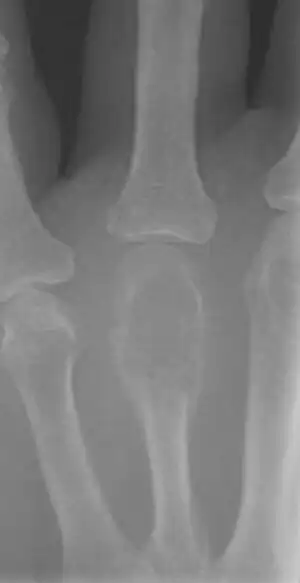

The key histomorphologic feature is, as the name of the entity suggests, (multinucleated) giant cells with up to a hundred nuclei that have prominent nucleoli. Surrounding mononuclear and small multinucleated cells have nuclei similar to those in the giant cells; this distinguishes the lesion from other osteogenic lesions which commonly have (benign) osteoclast-type giant cells. Soap-bubble appearance is a characteristic feature.

On X-ray, giant-cell tumors (GCTs) are lytic/lucent lesions that have an epiphyseal location and grow to the articular surface of the involved bone.[11] Radiologically the tumors may show characteristic 'soap bubble' appearance.[12] They are distinguishable from other bony tumors in that GCTs usually have a nonsclerotic and sharply defined border. About 5% of giant-cell tumors metastasize, usually to a lung, which may be benign metastasis,[13] when the diagnosis of giant-cell tumor is suspected, a chest X-ray or computed tomography may be needed. MRI can be used to assess intramedullary and soft tissue extension.